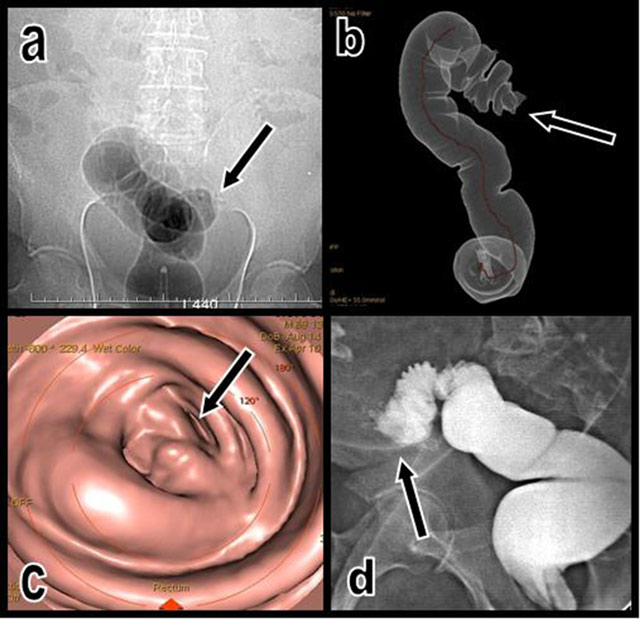

Figure 1

The topogram performed just after unsuccessful CO2 insufflation of the colon (a) illustrates an impassable colonic stenosis at the level of the junction between the sigmoid and descending colon (black arrow). A corresponding volume-rendering view (b) of the insufflated segment shows the abrupt cutoff (black arrow). Corresponding virtual endoscopic view of the cutoff (c). A classical colonic retrograde opacification obtained the next day after CT (d) also confirms the nearly complete cutoff of the colon proximal sigmoid; only a small amount of hydrosoluble contrast can pass through the stenosis (black arrow).